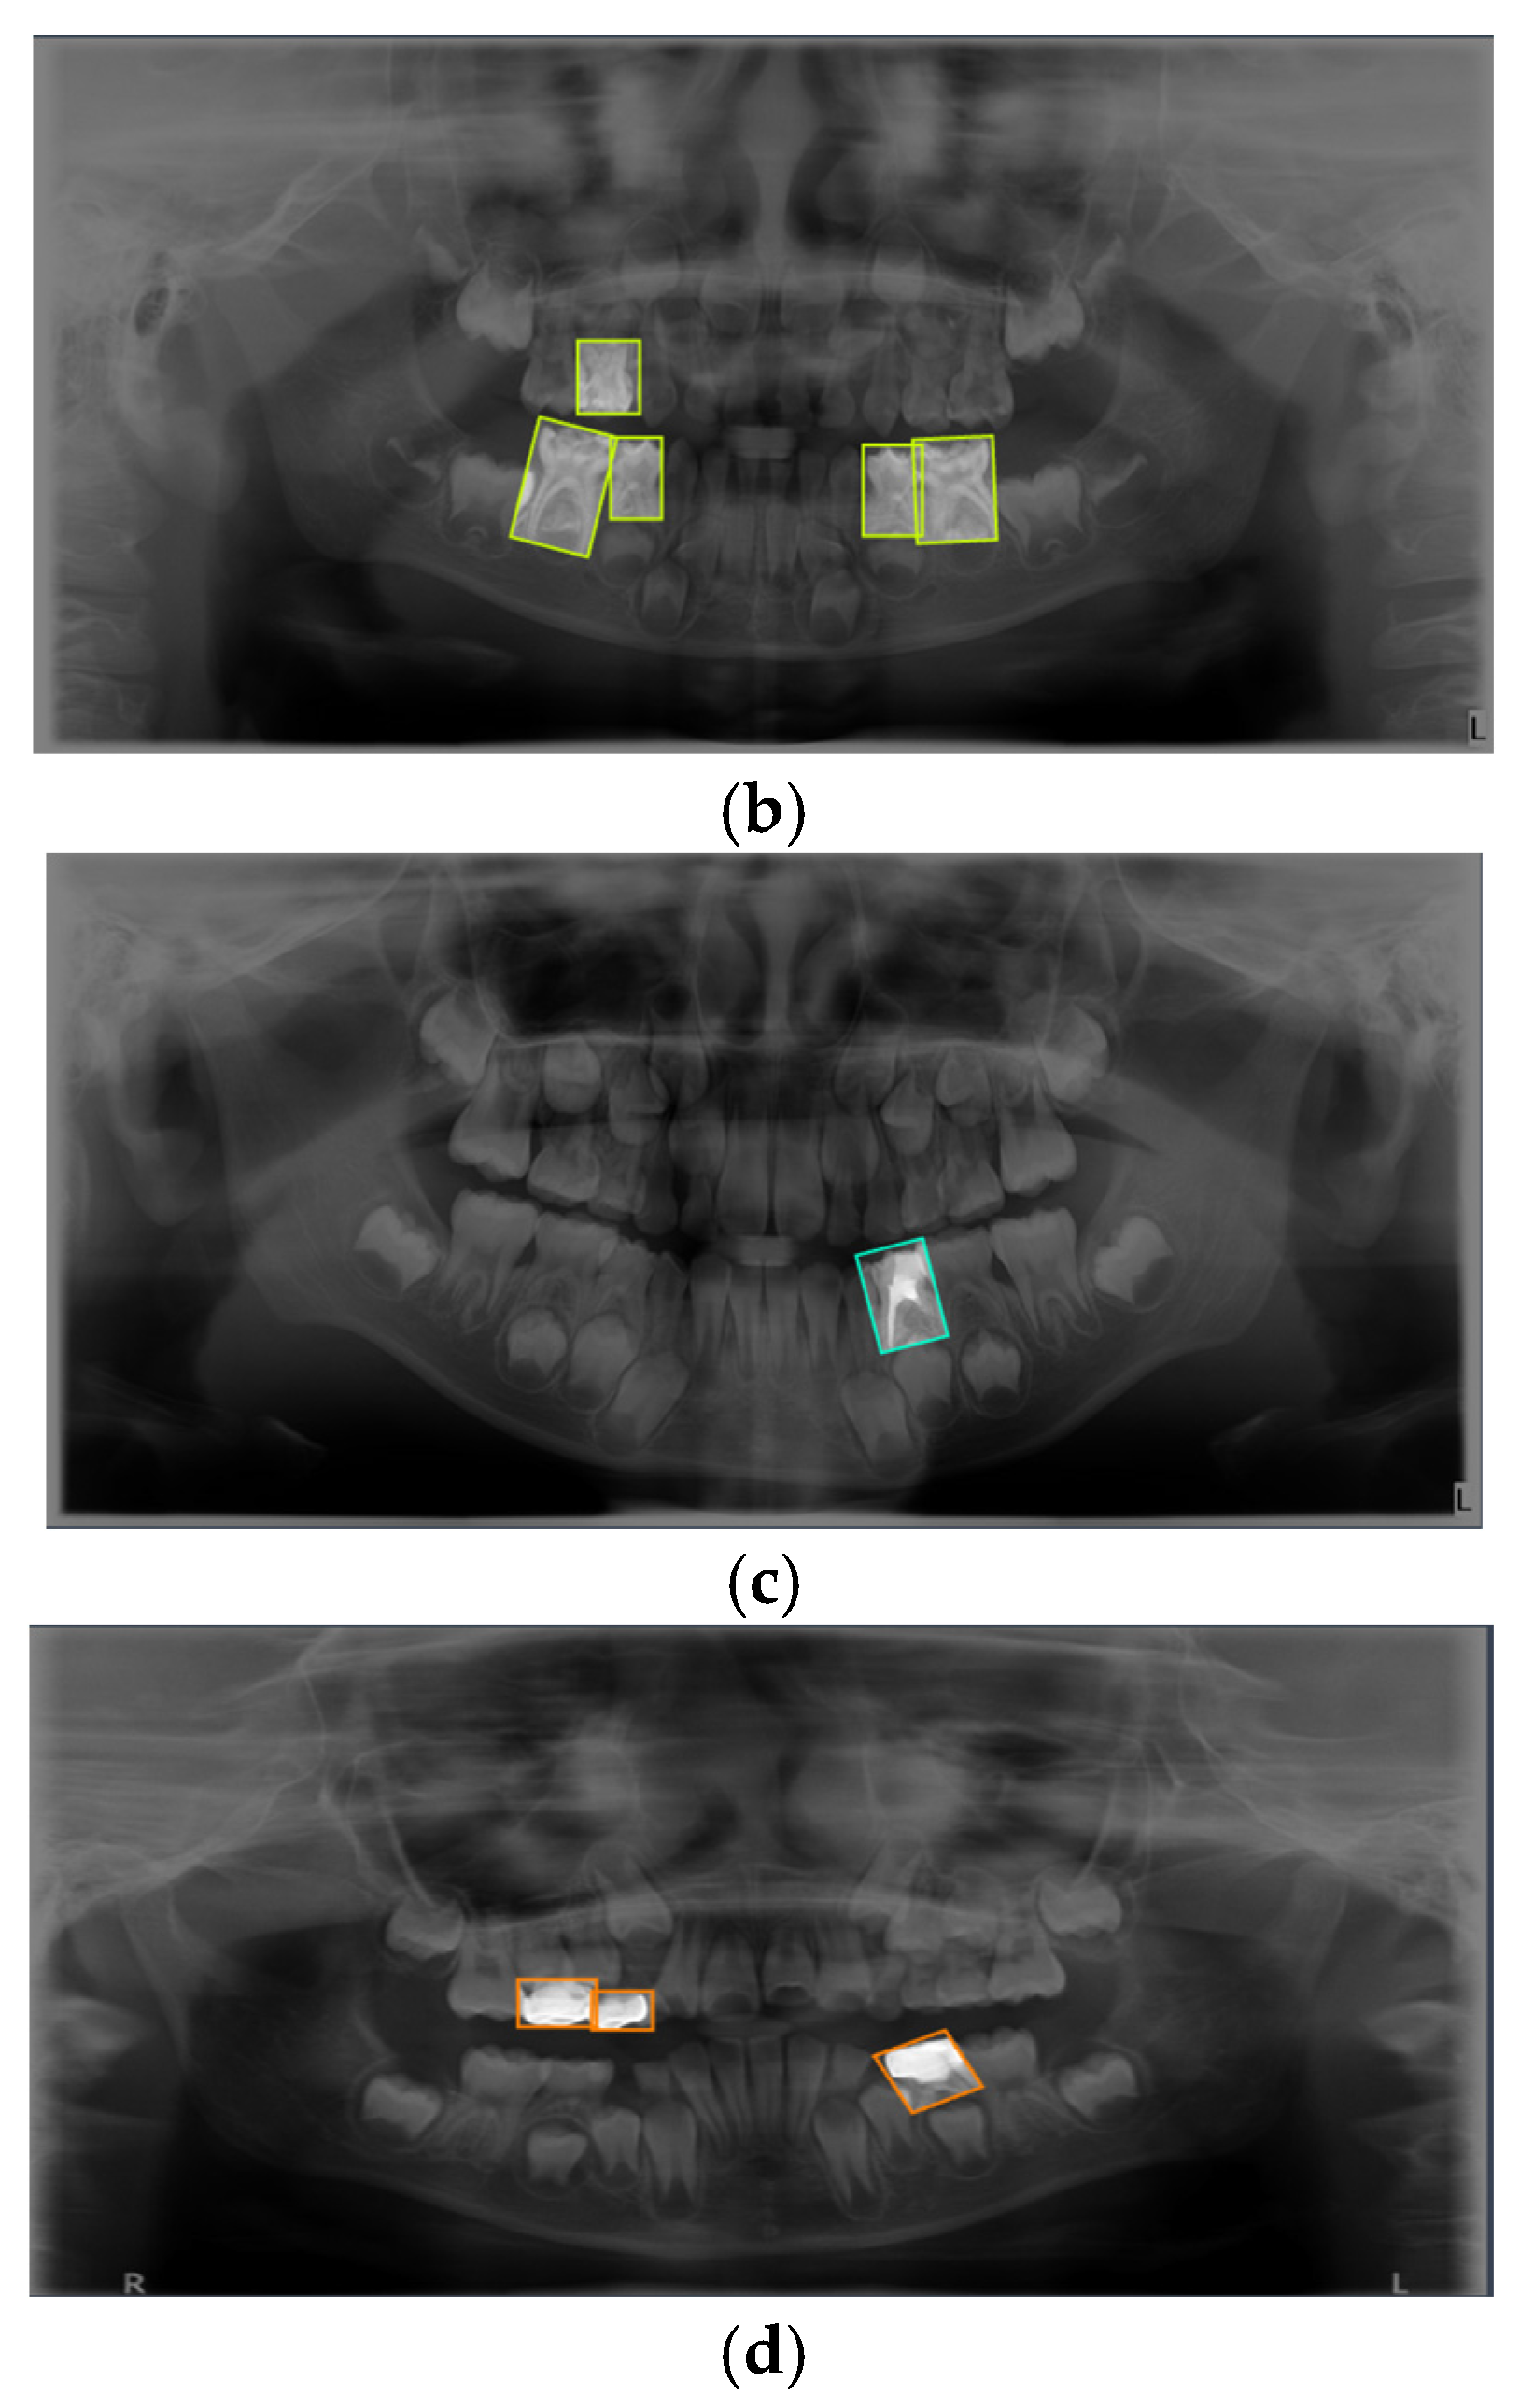

Figure 1. Representative examples of the four annotated dental conditions from the primary dataset. The images display examples of (a) Dental Caries, (b) Deciduous Tooth, (c) Root Canal Treatment, and (d) Pulpotomy. Bounding boxes indicate the ground-truth labels used for model training.

Figure 6. Examples of Successful Detection of YOLO Models for Different Dental Conditions. The images display representative examples of correct detections for (a) Dental Caries, (b) Deciduous Tooth, (c) Root Canal Treatment, and (d) Pulpotomy.